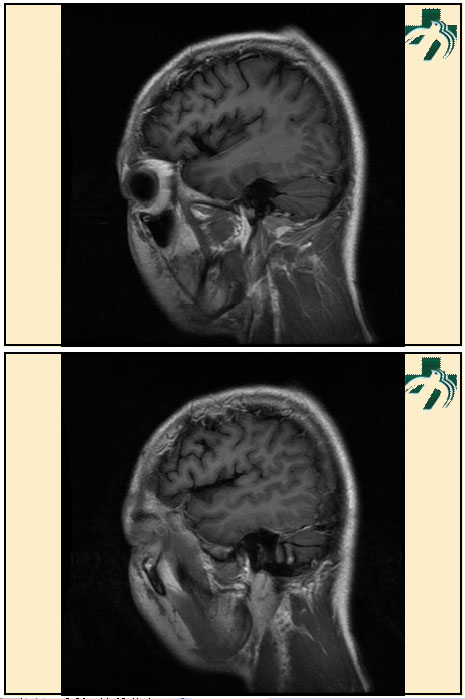

奴卡氏菌感染

第九期三博

读片会

病例之四

北京协和医院 提供

男性,22岁。自觉虫咬后皮疹、肢体麻木4月